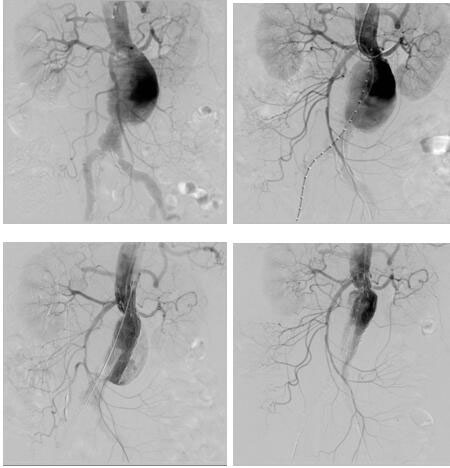

血管介入科完成我院首例腎下復(fù)雜型腹主動脈瘤腔內(nèi)修復(fù)

日前,血管介入科為一位患腎下復(fù)雜型腹主動脈瘤(左腎動脈距離瘤體僅4mm)74歲老年女性完成腎動脈煙囪+腹主動脈瘤覆膜支架腔內(nèi)隔絕術(shù),術(shù)后恢復(fù)良好。該患者基礎(chǔ)疾病多,已經(jīng)出現(xiàn)腹痛癥狀,腹主動脈瘤瘤體隨時有破裂風(fēng)險,但左腎動脈距離瘤體僅4mm,采取傳統(tǒng)開放手術(shù)(腹主動脈瘤切除+Y型人工血管置換+左腎動脈轉(zhuǎn)流術(shù))手術(shù)創(chuàng)傷大,手術(shù)風(fēng)險高,經(jīng)血管外科治療團(tuán)隊反復(fù)研究病例,并在院領(lǐng)導(dǎo)支持下,決定采取腔內(nèi)治療:先經(jīng)肱動脈穿刺置鞘于左腎動脈留置導(dǎo)絲,再經(jīng)雙側(cè)股動脈上導(dǎo)絲導(dǎo)管造影定位,在施放腹主動脈主體支架前先經(jīng)左肱動脈留置導(dǎo)絲導(dǎo)引下于左腎動脈置入VIABAHN支架保證左腎動脈供血,再釋放腹主動脈主體支架,解決了左腎動脈距離瘤體過近的問題。該例手術(shù)的完成,標(biāo)志著我院在腹主動脈瘤的腔內(nèi)治療跨入省內(nèi)領(lǐng)先行列。